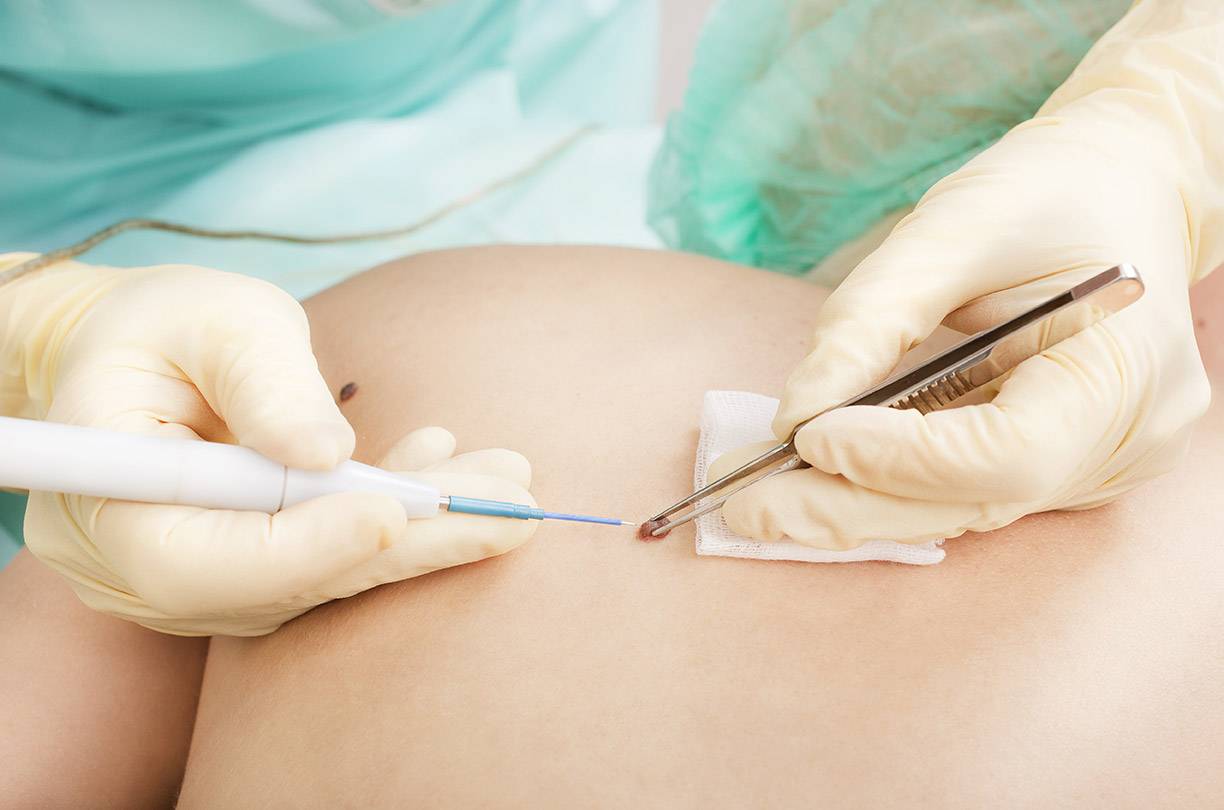

Фото: взятие маска на ВПЧ

Биопсия

Процедура заключается во взятии живых клеток ткани для подробного исследования и исключения онкологии, ведь удалять «плохие» папилломы нельзя, потому как может произойти цепная реакция и раковое заболевание, как результат этого.

Современные клиники располагают всем необходимым для проведения биопсии.

В случае если опасения не подтвердятся, можно перейти непосредственно к удалению новообразования.

Фото: метод криодеструкции

Фото: лазерное удаление